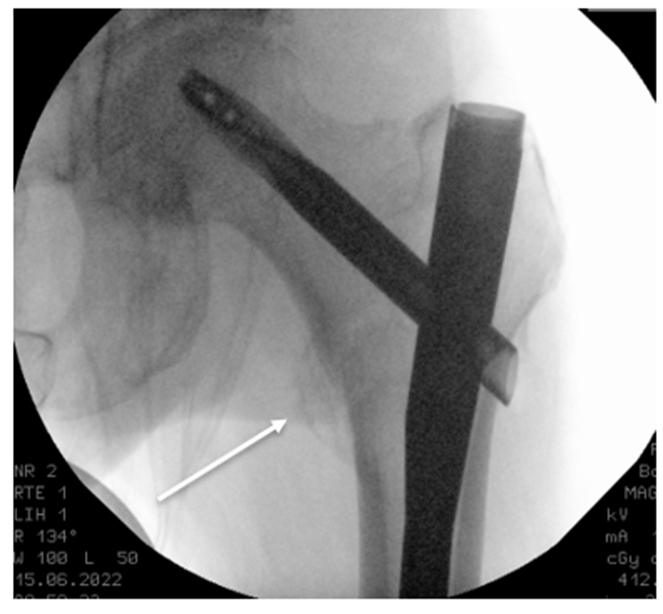

A 79-year-old female with a history of osteoporosis was admitted to the emergency department after tripping and falling on her left hip. Radiographs confirmed a pertrochanteric fracture with a non-displaced concomitant lesser trochanter fracture (Figure. 1), classified as AO 31.A1.3, according to the AO fracture classification system. The patient underwent closed reduction and intramedullary nailing (TFN-ADVANCED™ Proximal Femoral Nailing System, Depuys Synthes). Intraoperative fluoroscopy confirmed good fracture reduction and optimal implant placement (Figure. 2).

Figure 2: Intraoperative anteroposterior fluoroscopy imaging, showing a good reduction of the fracture without dislocation of the lesser trochanter (arrow).